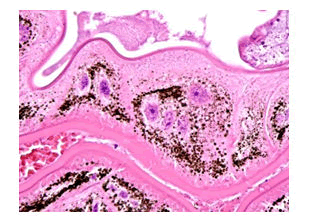

Figure 4: Low power haematoxylin and eosin (H and E) stained image of the eyeball. There is a central eosinophilic exudates and inflammatory thickening of the choroids

Figure 5: Higher power H and E of the choroid shows a necrotic tract (asterisk), cuffed by granulomatous inflammation (arrow).

Figure 6: H and E-The granulomatous inflammation is in turn cuffed by a dense eosinophilic inflammatory response.

Figure 7: Low power H and E shows an infective agent in the choroid (arrowed). PE=retinal pigment epithelium.

Figure 8: Higher power H and E showing an agent with an outer cuticle and an irregular hyaline branching inner tube.

Figure 9: Higher power H and E of the inner irregular hyaline branching tube.

Figure 10: The lining cells of the inner tube are multinucleate and contain brown pigment.